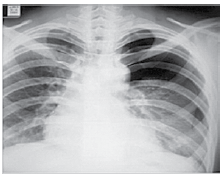

Homem de 62 anos, com história de insuficiência cardíacagrave, é internado devido um quadro dispneico. Pressão arterial: 140 x 115 mmHg, pulso: 122 bpm; ausculta pulmonar: crepitações até ápices bilateralmente. Radiografia de tórax é realizada e mostrada a seguir.

Enunciado 3309348-1

Em relação ao quadro clínico, é correto afirmar: